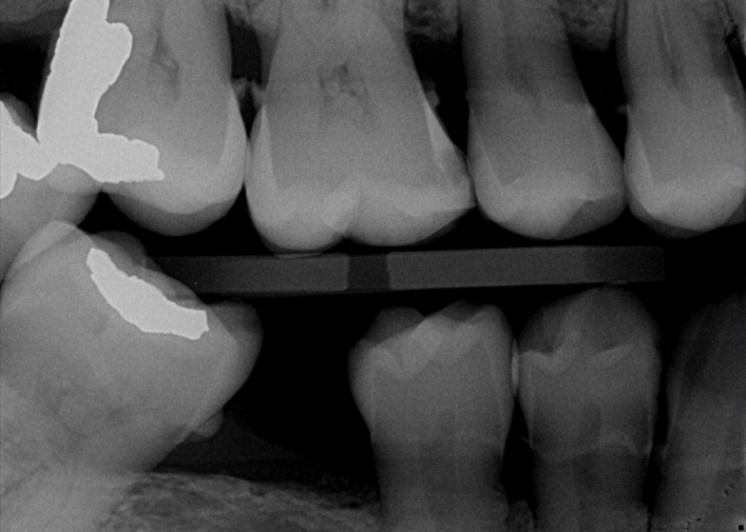

Through years of training, our dentists are experts in reading imaging results, able to see decay, cavities and more on your X-rays. For the lay person, these results are often much more difficult to interpret, even when the dentist is pointing out what he or she is seeing. OVERJET technology analyzes the X-ray images similar to how the dentist would, then overlays that image with colored highlighting and measurements to illuminate any diseases, conditions and more. Essentially, this allows our patients to see what the dentist sees!

X-Ray

X-Ray with OVERJET